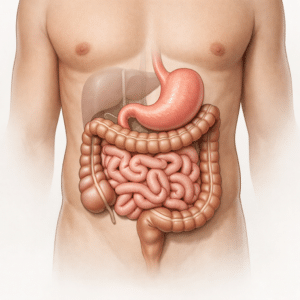

Understanding Abdominal Pain: What Is the Cause?

Abdominal pain is something that almost everyone experiences at some point in…